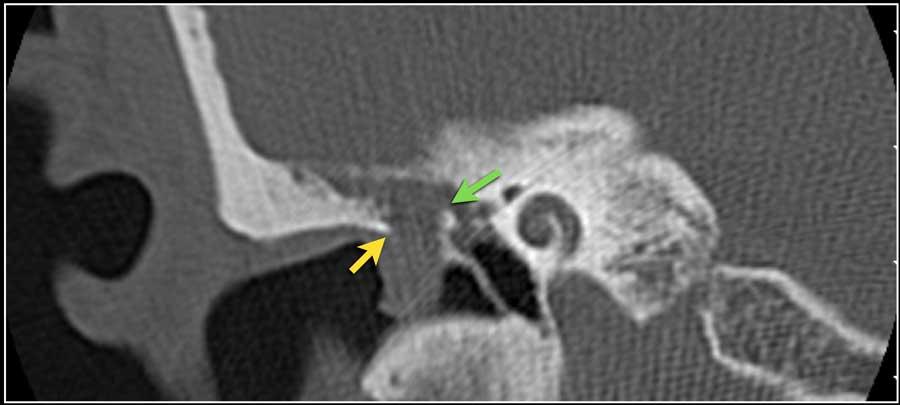

Hình ảnh một bệnh nhân có cholesteatoma.

Có một khối mô mềm ở vùng thượng nhĩ.

Lưu ý hình ảnh thủng màng nhĩ (mũi tên vàng) và bào mòn ống bán khuyên ngoài (mũi tên đỏ).

Scutum bị tù mòn.